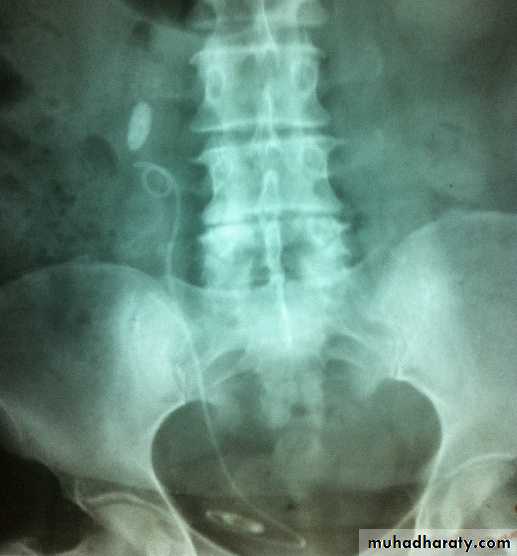

KUB

Multiple bilateral renal stonesStaghorn stone needs PCNL